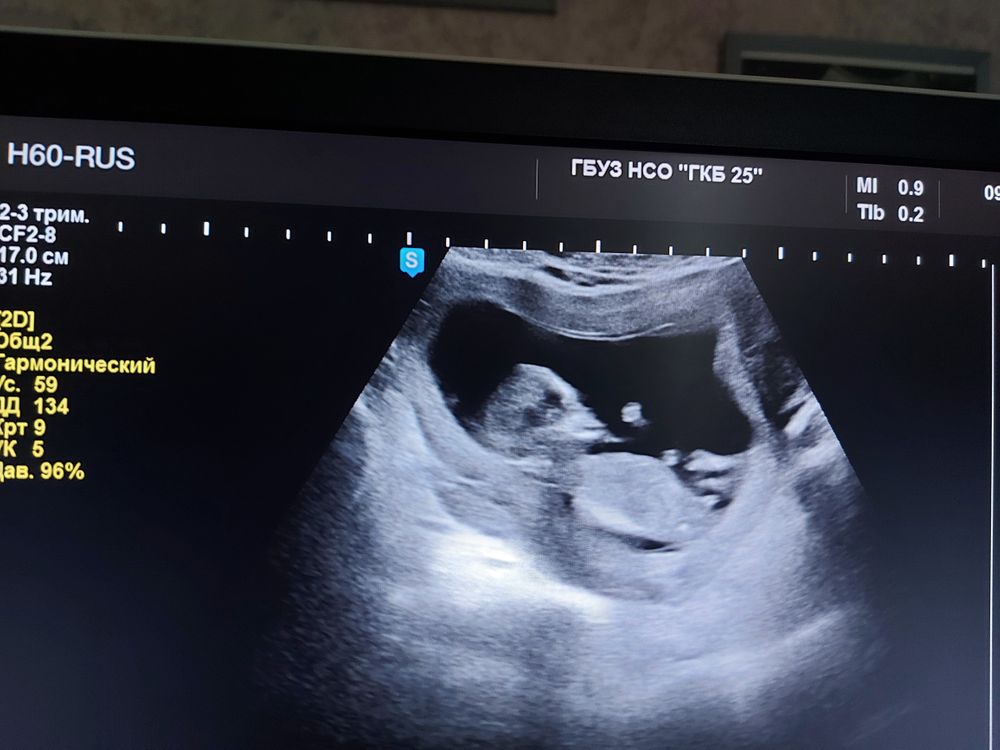

Врач Узи предположила мальчика,из за длины половых органов,но также она сказала что вот эти полоски они ровные,как у девочки, может просто что половые губы на данном сроке могут быть длинные, в итоге 50/50 по